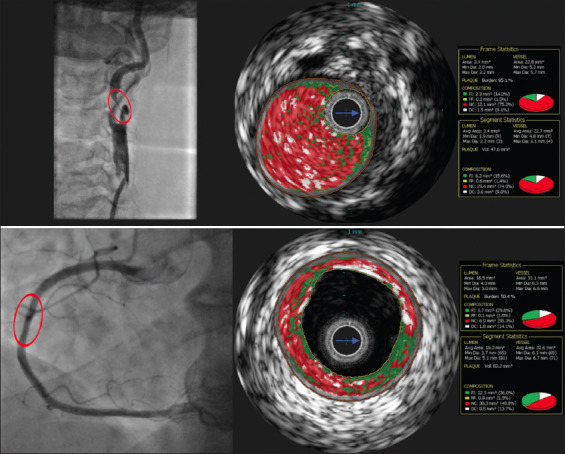

Background and aim: Atherosclerosis is considered to be a systemic disease; however, evidence exists on the heterogeneous nature of atherosclerotic disease. To date, continuous research seeks to determine the morphological differences between carotid and coronary artery disease. This study aimed to evaluate the relationship of morphological characteristics assessed by virtual histology intravascular ultrasound (VH-IVUS) between carotid and coronary plaque composition among patients with and without a history of cerebrovascular events.

Methods: This study was a single-center prospective study (n = 100; age 69.6 ± 8.4). All patients were scheduled for carotid or coronary artery stenting and underwent VH-IVUS examination of the carotid and coronary arteries before intervention.

Results: There was a modest, but statistically significant correlation between the carotid and coronary necrotic core ([NC] r = 0.46, P < 0.01), fibrofatty ([FF] r = 0.38, P < 0.01), dense calcium (r = 0.56, P < 0.01), and fibrous (r = 0.42, P < 0.01) plaque composition. The high amount of NC was detected in both arteries of the carotid artery stenting (CAS) group with higher proportion in the coronary artery (20.2% ± 9.4 % vs. 22.7% ± 6.8%, P = 0.02). More fibrolipid content was observed in carotid plaque compared to coronary (19.6% ± 9.9% vs. 12.2% ± 8.1%, P < 0.01). Patients with a history of cerebrovascular events had a numerically greater proportion of necrotic tissue in the carotid artery compared to asymptomatic and symptomatic CAS group patients (23.5% ± 10.7% vs. 18.9% ± 8.2% and 18.7% ± 9.5%, P = 0.11).

Conclusion: The percentage of all analyzed plaque components was moderately correlated between coronary and carotid artery plaques. Nevertheless, the proportion of NC plaque tissue was greater in the coronary arteries, while the carotid arteries showed more %FF atherosclerotic lesions. CAS group patients with a history of cerebrovascular events had a tendency of greater proportion of necrotic tissue in analyzed carotid plaques compared to others in the CAS group.

Relevance for patients: In this study, we found that patients with a history of cerebrovascular event had a tendency of increased NC content in culprit lesion of carotid artery. Complementary use of non-invasive and invasive imaging modalities allows to detect high-risk atherosclerotic plaques and adjust treatment strategy.